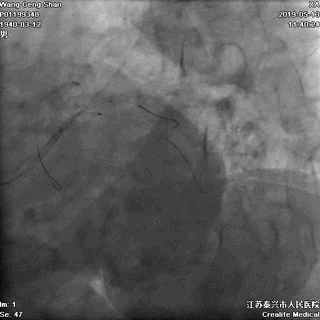

06 LM-LAD支架后扩张

交换回旋支导丝,非顺应性球囊顺序高压扩张

07 LM支架近段优化(POT)

左主干近段用大一号非顺应性球囊行高压扩张

IVUS评估,支架贴壁良好。